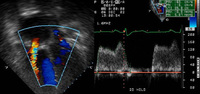

Tricuspid stenosis

Haemodynamic tracings obtained during cardiac catheterisation from a woman with moderate to severe rheumatic tricuspid valve stenosis

From the personal collection of Martin Bocks; used with permission